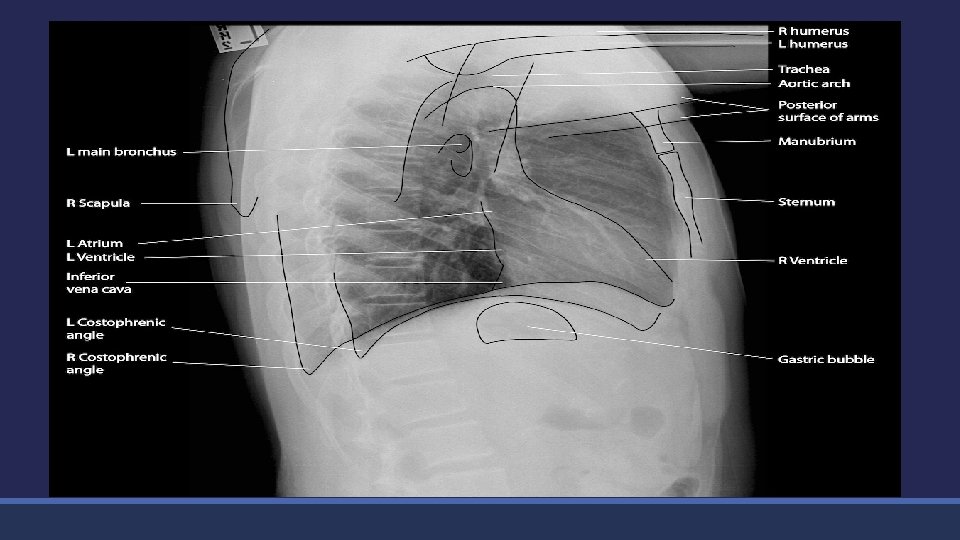

Chest X-ray